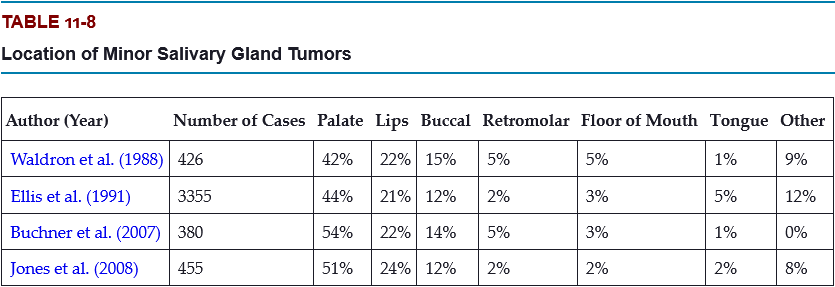

What is the most frequent site for a minor salivary gland tumor?

- lip

- buccal mucosa

- palate

- floor of the mouth

- tongue

- retromolar

C. palate

Most of these occur on the posterior lateral hard or soft palate, which have the greatest concentration of glands.

Which is a more common location for minor salivary gland tumors, the upper lip or the lower lip?

Labial tumors are significantly more common in the upper lip, which accounts for 74% to 87% of all lip tumors.

Which are the three most likely sites for a malignant minor salivary gland tumor?

- lip

- floor of the mouth

- tongue

- palate

- buccal mucosa

- retromolar

B, C, and F

Up to 95% of retromolar tumors are malignant because of a predominance of mucoepidermoid carcinomas; most tumors in the floor of the mouth and tongue are also malignant.